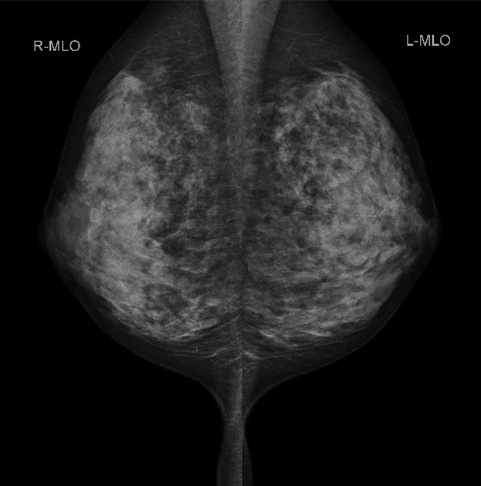

乳房撮影装置(マンモグラフィ)

マンモグラフィ(MMG)とは、乳房専用のX線撮影のことです。乳房を圧迫して撮影するため痛みを伴う場合が多いですが、乳房を薄くして撮影することにより被ばくが軽減し、きれいな画像を得ることが出来ます。そのため検査を受けられる方のご理解、ご協力がとても大切になります。当院の装置は3Dマンモグラフィ(トモシンセシス)が撮影できる装置を導入しております。従来と比べて高精細な画像が得られるようになりました。診察にあたっても5Mの高精細モニターを使用しています。

また当院では「検診マンモグラフィ撮影認定診療放射線技師」が在籍しており、検査は女性技師が担当いたします。